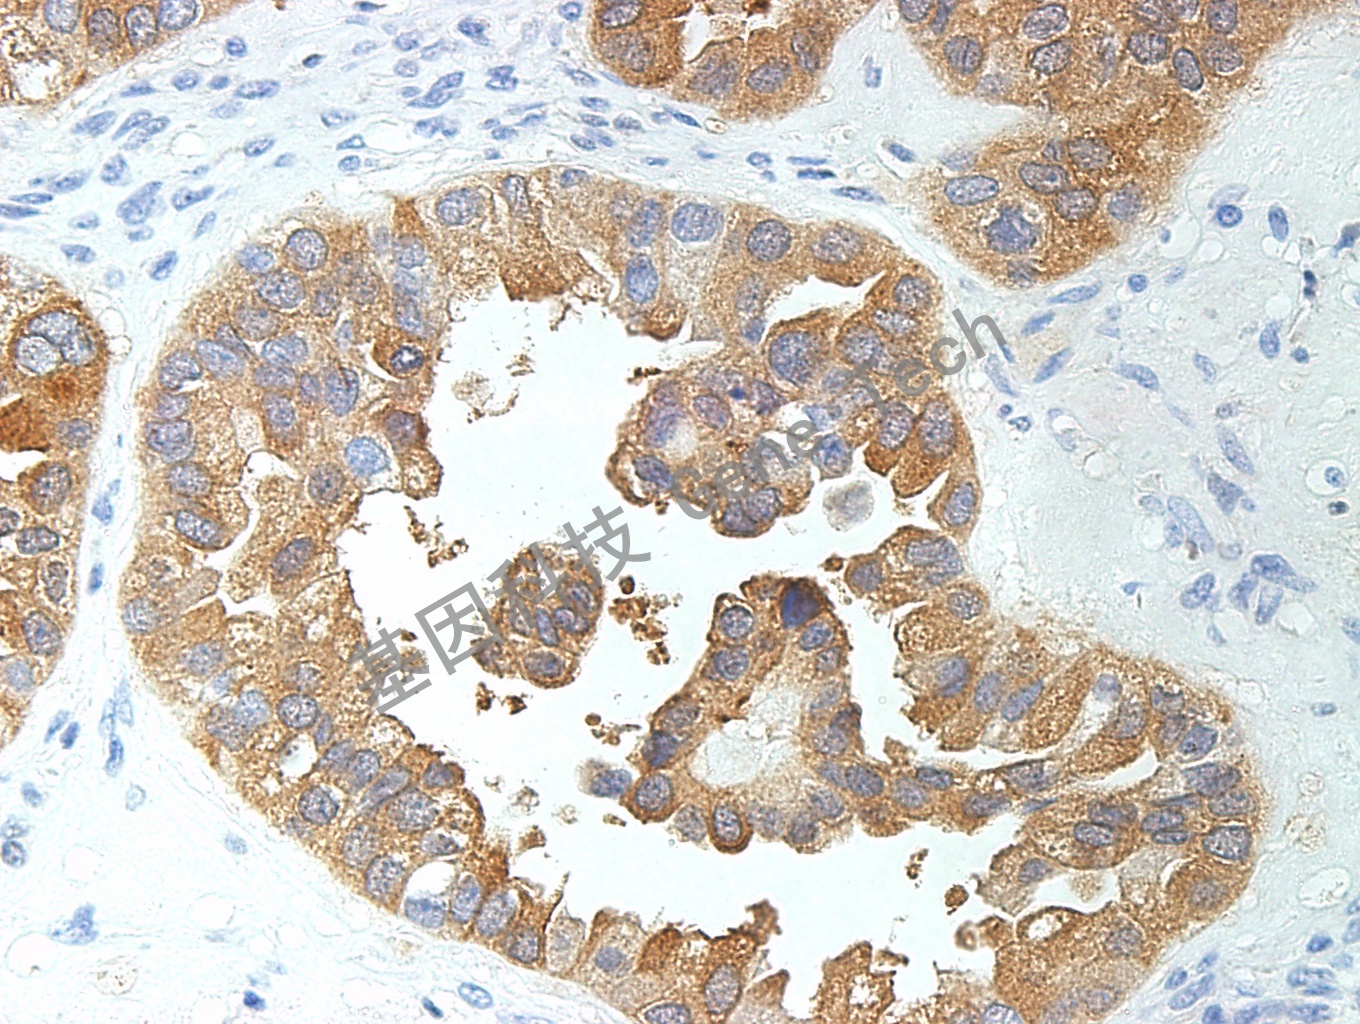

肝癌石蜡切片,用 Glypican-3(GT2068)染色,细胞浆阳性,DAB 显色。

肝细胞癌石蜡切片,用 Glypican-3(GT2068)染色,细胞浆阳性,DAB 显色。

卵巢透明细胞癌石蜡切片,用 Glypican-3(GT2068)染色,细胞浆阳性,DAB 显色。